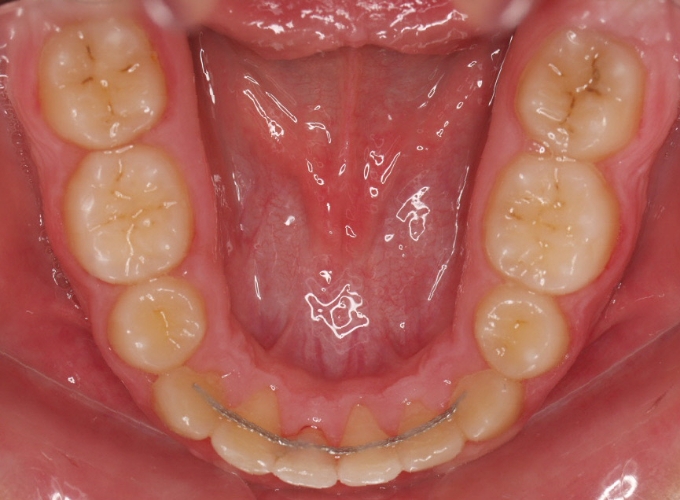

Plan tratamiento:

– Decidimos extraer 14.24.34.44

– Colocamos microtornillo lado izquierdo

– Gomas en triángulo para conseguir oclusión perfecta.

Fotos fin tratamiento: